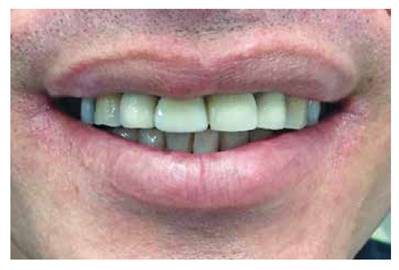

Al paciente se le deja la pieza ferulizada con el mismo alambre de ortodoncia y con los brackets por unos tres a cinco meses con la finalidad de evitar una nueva recidiva. Posteriormente se remueve la ortodoncia y se procede a efectuar la rehabilitación del central superior derecho. Se cementa un poste de fibra de vidrio en el conducto radicular y se confecciona un muñón (con el material Duo Core) el cual finalmente es preparado para recibir una corona de metal porcelana y se le toma una radiografía periapical final. (Figuras 15A y 15B)

Figura 15A: Restauración con una corona de metal porcelana.